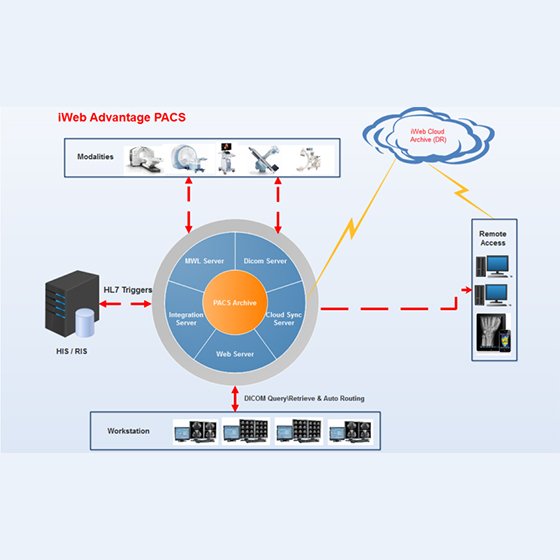

IWEB - TELE RADIOL

IWEB ADV PACS